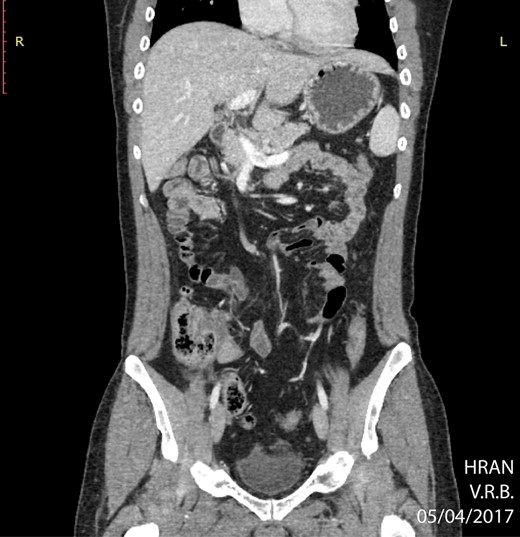

The surgery was indicated at the moment of clinical diagnosis, dismissing any imaging techniques. Even though CT-scanning is not mandatory, it grants over 90% sensitivity and specificity for acute appendicitis and helps with other differential diagnoses [6]. In this case, the CT-scan was only solicited after the lymphoma diagnosis, revealing a bulky and extensive mass in the right iliac fossa, poorly delimited, along with right pyeloureteral dilation. A probable diagnosis of appendiceal neoplasms can be made based on the increased diameter of the appendix shown on CT-scans (>3 cm), which is out of proportion for a non-tumoral appendicitis [5]. The specificity for lymphoma increases when abdominal lymphadenopathy or aneurysmal dilation of the appendiceal lumen are present [7]. These findings corroborate with a pre-operative suspicion of a primary appendiceal neoplasm.

CT of abdomen (coronal plane) highlighting an extensive, ill-defined mass localized in the right iliac fossa (circle) (02/09/16).